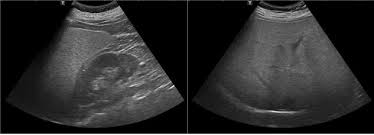

이런 경우 간장질환 의심을 미루지 마시고, 빠른 혈액 검사나 초음파 검사를 받아보는 것이 좋습니다. 조기 발견이 예후에 큰 영향을 주기 때문이에요.